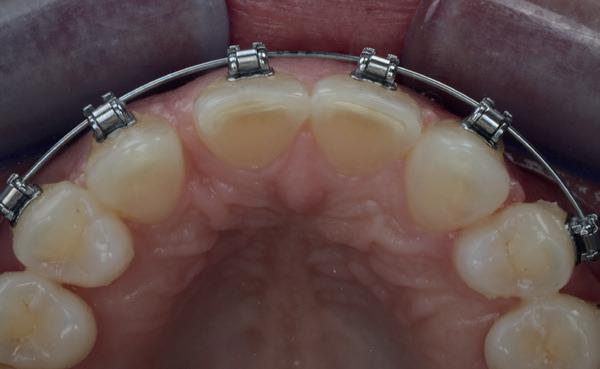

3. Vaste apparatuur voor torque 12 en 22

4. OPT radices 12 en 22 divergeren na orthodontische behandeling

van de patiënt, om eerst weer vaste apparatuur terug te plaatsen om de radices in een divergerende stand te plaatsen. Gelukkig verliep deze behandeling voorspoedig. (afbeelding 2 -4). Het volgende behandelplan werd gemaakt:

• Intra-orale scan voor studiemodellen, proefopstelling en beoordelen ruimte palatinaal

Vervaardigen essix retainer met dummies waarbij er een emergence profile van de 11 en 21 werd gevormd door eivormige dummies 4 mm in de gingiva te plaatsen

• Aanvulling zachte weefsels met de VISTA techniek en een vrij gingivatransplantaat uit het palatum links en direct dragen van de essix retainer

Na 4 weken intra-orale scan voor de etsbrug en kleurbepaling bij de technicus

• Plaatsen van de etsbrug met een composietcement

Voordat er gescand kon worden voor een etsbrug, werd een studiemodel vervaardigd om met de technicus te overleggen of er voldoende ruimte was voor 2 centrale incisieven in de mesio-distale zin en of er voldoende ruimte was in occlusie voor de vleugels van de etsbrug. Er hoeft enkel nog aan de 12 en 22 pala-

5. Beginsituatie voor behandeling

13. Occlusaal beeld verdikking van de zachte weefsels

19. Etsbrug palatinaal